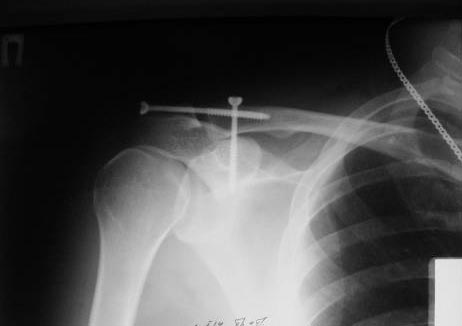

А зачем фиксировать по Веберу, если можно двумя винтами чрескожно.

В начале использовали канюлированные, а затем обычные (канюлированные жалко). Фото в приложении. Операция под ЭОПом.

Травма свежая.

Вы всегда выполняется такую гиперкоррекцию как представлено на рентгенограммах?

5. Насчет гиперкоррекции- согласен. В данном случае немного перестарался. На функциональный результат никак не повлияло. Пациент выписан к труду.